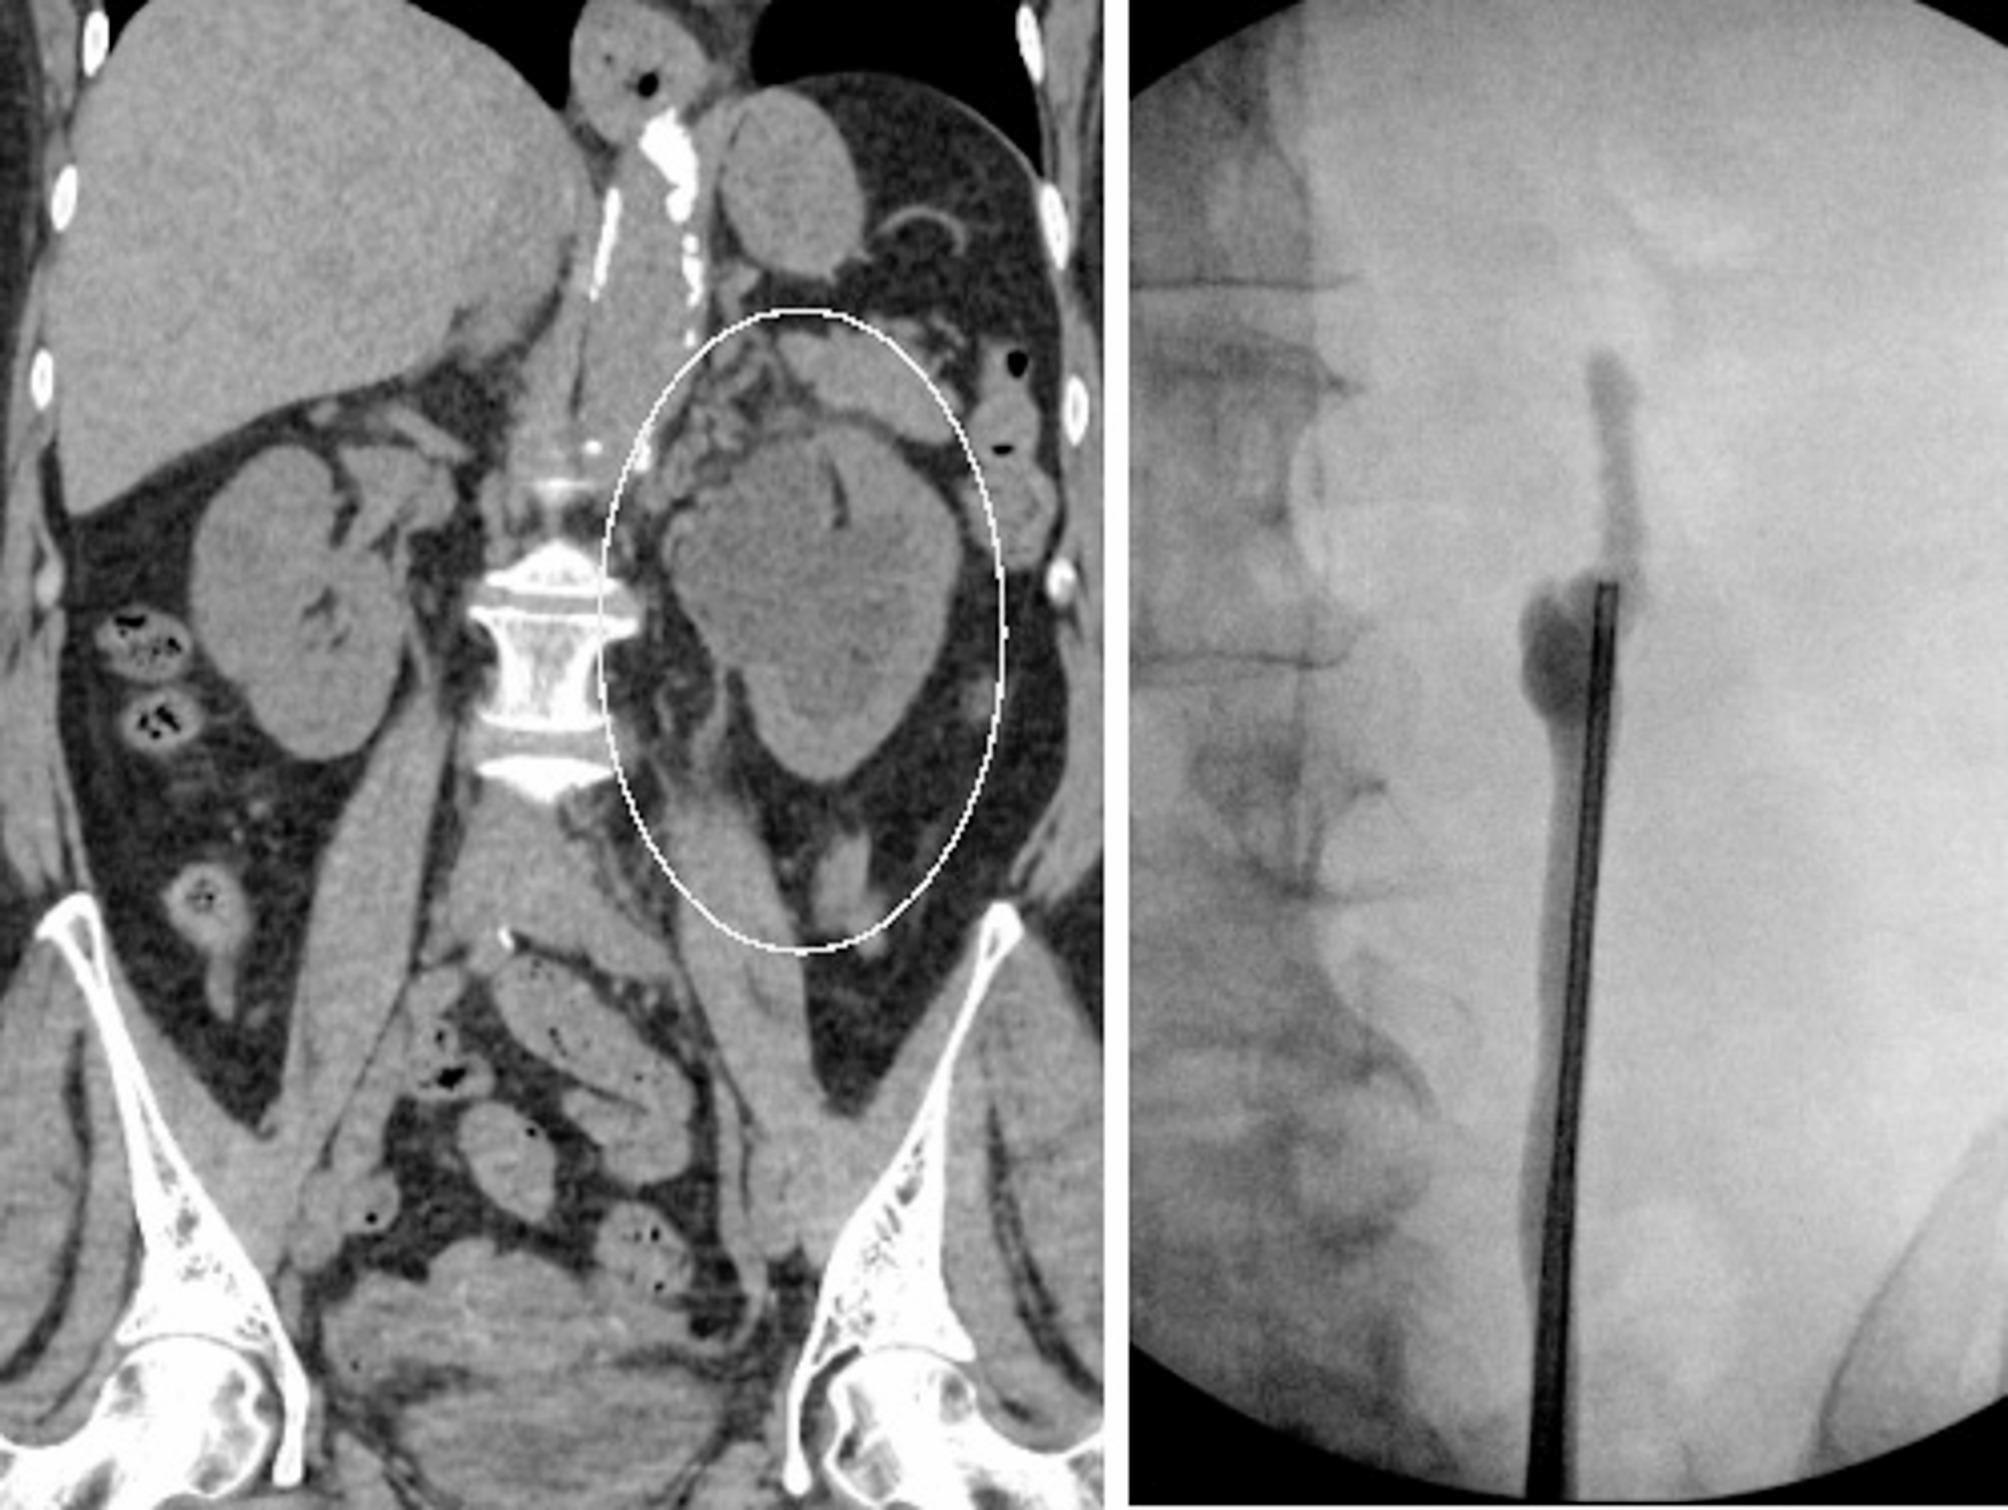

Introduction: Complex proximal ureteral strictures can pose significant surgical challenges, including long or obliterated strictures, inability to perform primary anastomotic repairs, fixed renal pelvis, impaired vascular supply from prior surgeries, and poor healing of the proximal ureter. We describe a novel surgical technique for addressing these issues.

Methods: Our technique involves a combination of ureterolysis, renal pelvis flap creation, and buccal mucosal grafting. The procedure commences with exposure of the renal pelvis, creation of a U-shaped renal pelvis flap as the posterior plate and a buccal mucosa graft as the anterior plate. The omentum is then secured to provide a vascular bed for the graft.

Results: A total of 4 patients were included, with a mean age of 49 years. The median operating time was 4.08 h. The median post-operative length of stay was 1.5 days. At initial mean radiographic follow-up period of 3.2 months the success rate of the reconstruction was 100% with all patients demonstrating complete resolution of symptoms and radiographic improvement. Long-term follow-up was on average 22.3 months with sustained stability/improvement in radiographic hydronephrosis and symptoms, with no evidence of stricture recurrence. There were no donor site complications.

Conclusion: This novel surgical technique, involving ureteroplasty with a renal pelvis flap augmentation and buccal mucosal graft (RPFA-BMG), proves effective for complex proximal ureteral reconstruction. It is particularly suitable for long proximal obliterated strictures that require a combination of tissue transfer techniques for successful ureteral reconstruction and achievement of physiologic drainage.